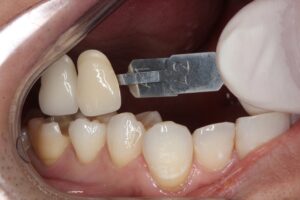

歯を色を記録します。

その方の歯の色に合わせて、歯科技工士がセラミックの詰め物を製作します。

後日セラミックがセットされた状態です☟

綺麗な歯に仕上がりました(^^)/

どこを治療したのか分からないように歯の形と色を再現し、

隙間の無いようにピッタリと一体化させています。